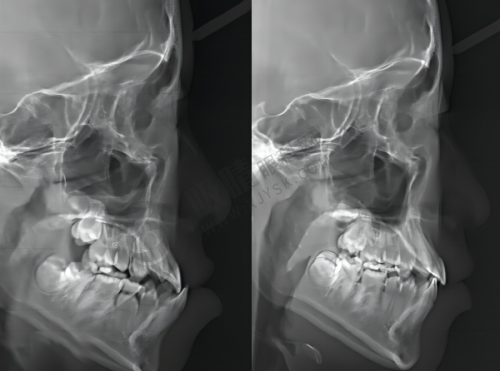

操作方式简单:进行隐适美矫正时,患者只需要先拍一张全景图,医生会根据全景图的情况为患者定制合适的隐形牙套。之后,患者按照医生的嘱咐佩戴牙套即可,无需花费太多时间在治疗过程中。